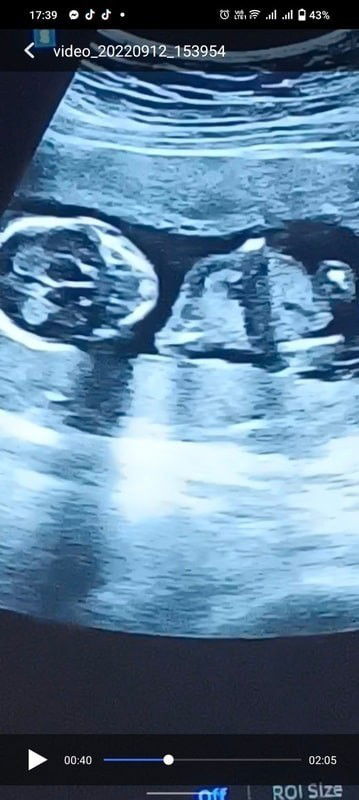

What is the Gender?

Mga Mommies, I'm currently 14 weeks right now and sinilip ni OB ang gender ni baby today. Palagay nyo po anong gender nya? Yung nasa right side po nandun ang gender pero di ko sya masure ayaw pa fin kasi sbihin ni OB next Ultrasound na daw, pero nakita nya na kung anong gender. First to comment the right answer will get 100 pesos Gcash pag confirm na po Gender nya by my next Ultrasound this coming October 3 🤗